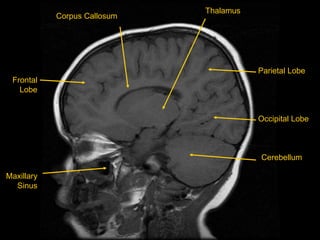

MRI BRAIN :SAGITTAL SECTIONS

HT

Frontal

Lobe

Maxillary

Sinus

Parietal Lobe

Occipital Lobe

Corpus Callosum

Thalamus

Cerebellum